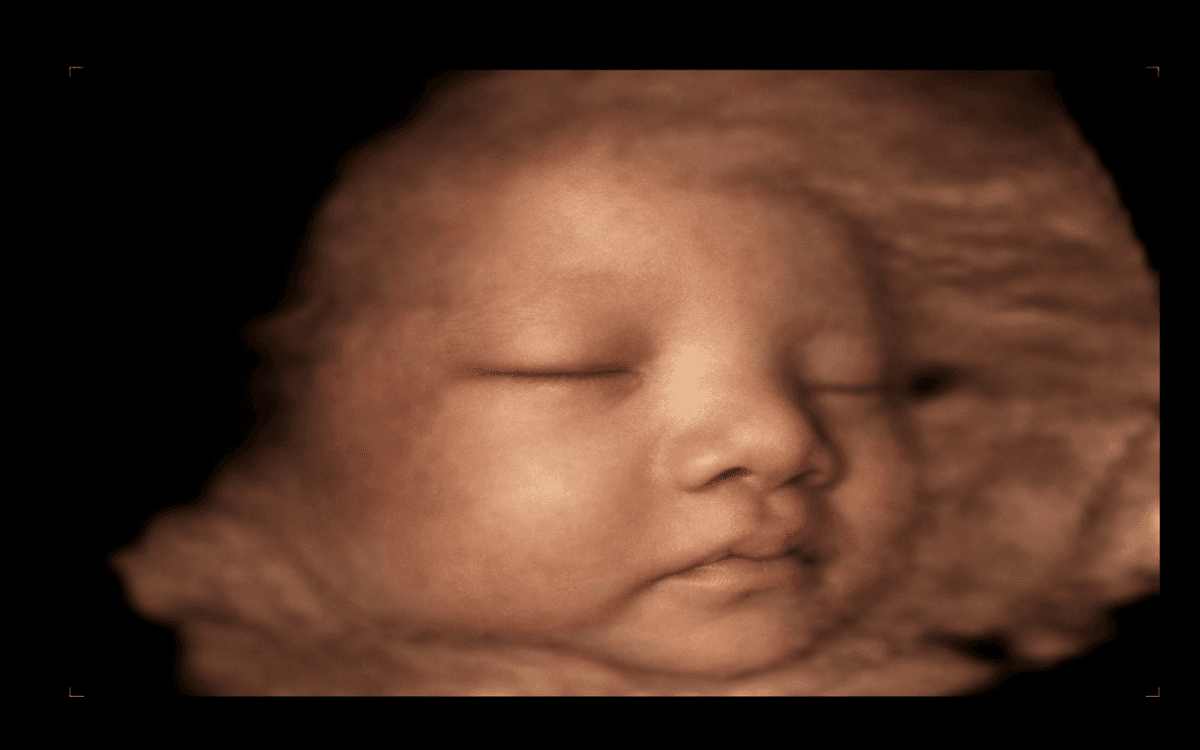

Vuốt để xem sự khác biệt giữa ảnh siêu âm gốc và hình ảnh AI làm nét